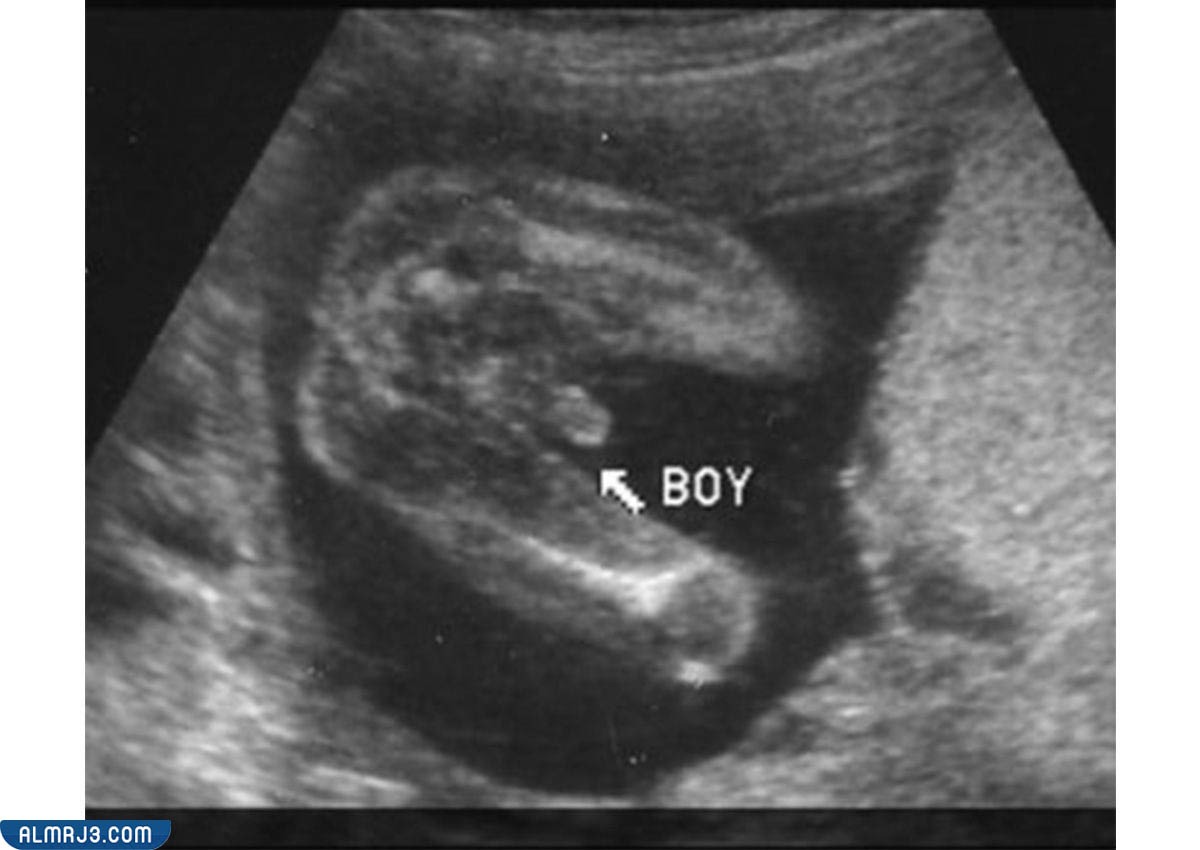

الفرق بين سونار البنت والولد في الشهر الرابع

تساعد أجهزة السونار في توضيح عدد الأجنة الموجود داخل الرحم، كما يساعد في توضيح نوع الجنين بمنتهى السهولة ومع اكتمال ووضوح الأعضاء التناسلية، ويظهر الفرق بين سونار البنت والولد في الآتي:

- أما الجنين الذكر فيمتلك العضو الذكري وذلك بالإضافة إلى الخصيتين.

شكل الجنين داخل السونار في الشهر الرابع

يختلف شكل الجنين الذكر في السونار عن شكل الجنين الأنثى، ويظهر ذلك الأمر بطريقة واضحة في الآتي:[2]

شكل الجنين الذكر

يمتلك الذكر العضو الذكري مع خصيتين ويظهر ذلك بوضوح في الشهر الخامس من الحمل.